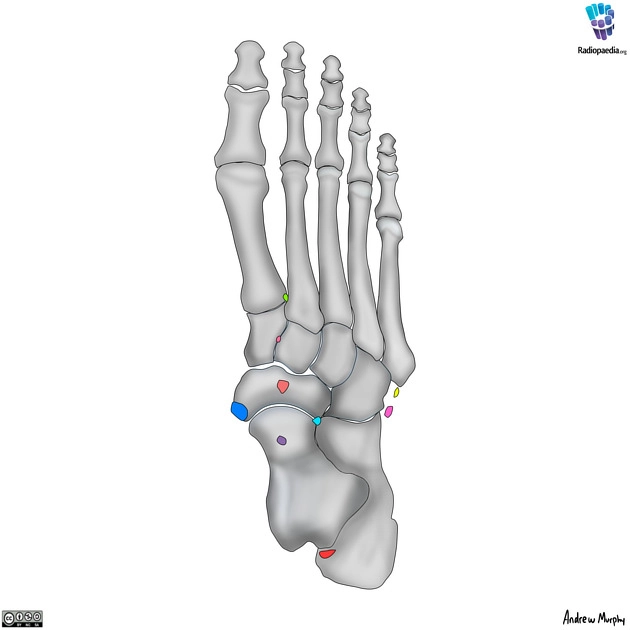

Xương phụ ở bàn chân (Accessory ossicles of the foot)